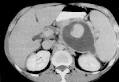

Pseudoquiste pancreático

Pseudoquiste pancreático es un saco lleno de líquido en el abdomen, que también puede contener tejido del páncreas, enzimas pancreáticas y sangre recubierto por una pared no epitelizada que se produce como resultado de una pancreatitis aguda, pancreatitis crónica, traumatismo pancreático u obstrucción del conducto pancreático. El páncreas es un órgano localizado detrás del estómago que produce químicos (llamados enzimas) necesarios para digerir el alimento

Signos y exámenes

El médico puede palpar el abdomen para sentir el seudoquiste, el cual se aprecia como una masa en la parte media o superior izquierda del abdomen. Los exámenes que pueden ayudar a diagnosticar el seudoquiste pancreático son:

- Tomografía computarizada del abdomen

- Resonancia magnética del abdomen

- Ecografía abdominal